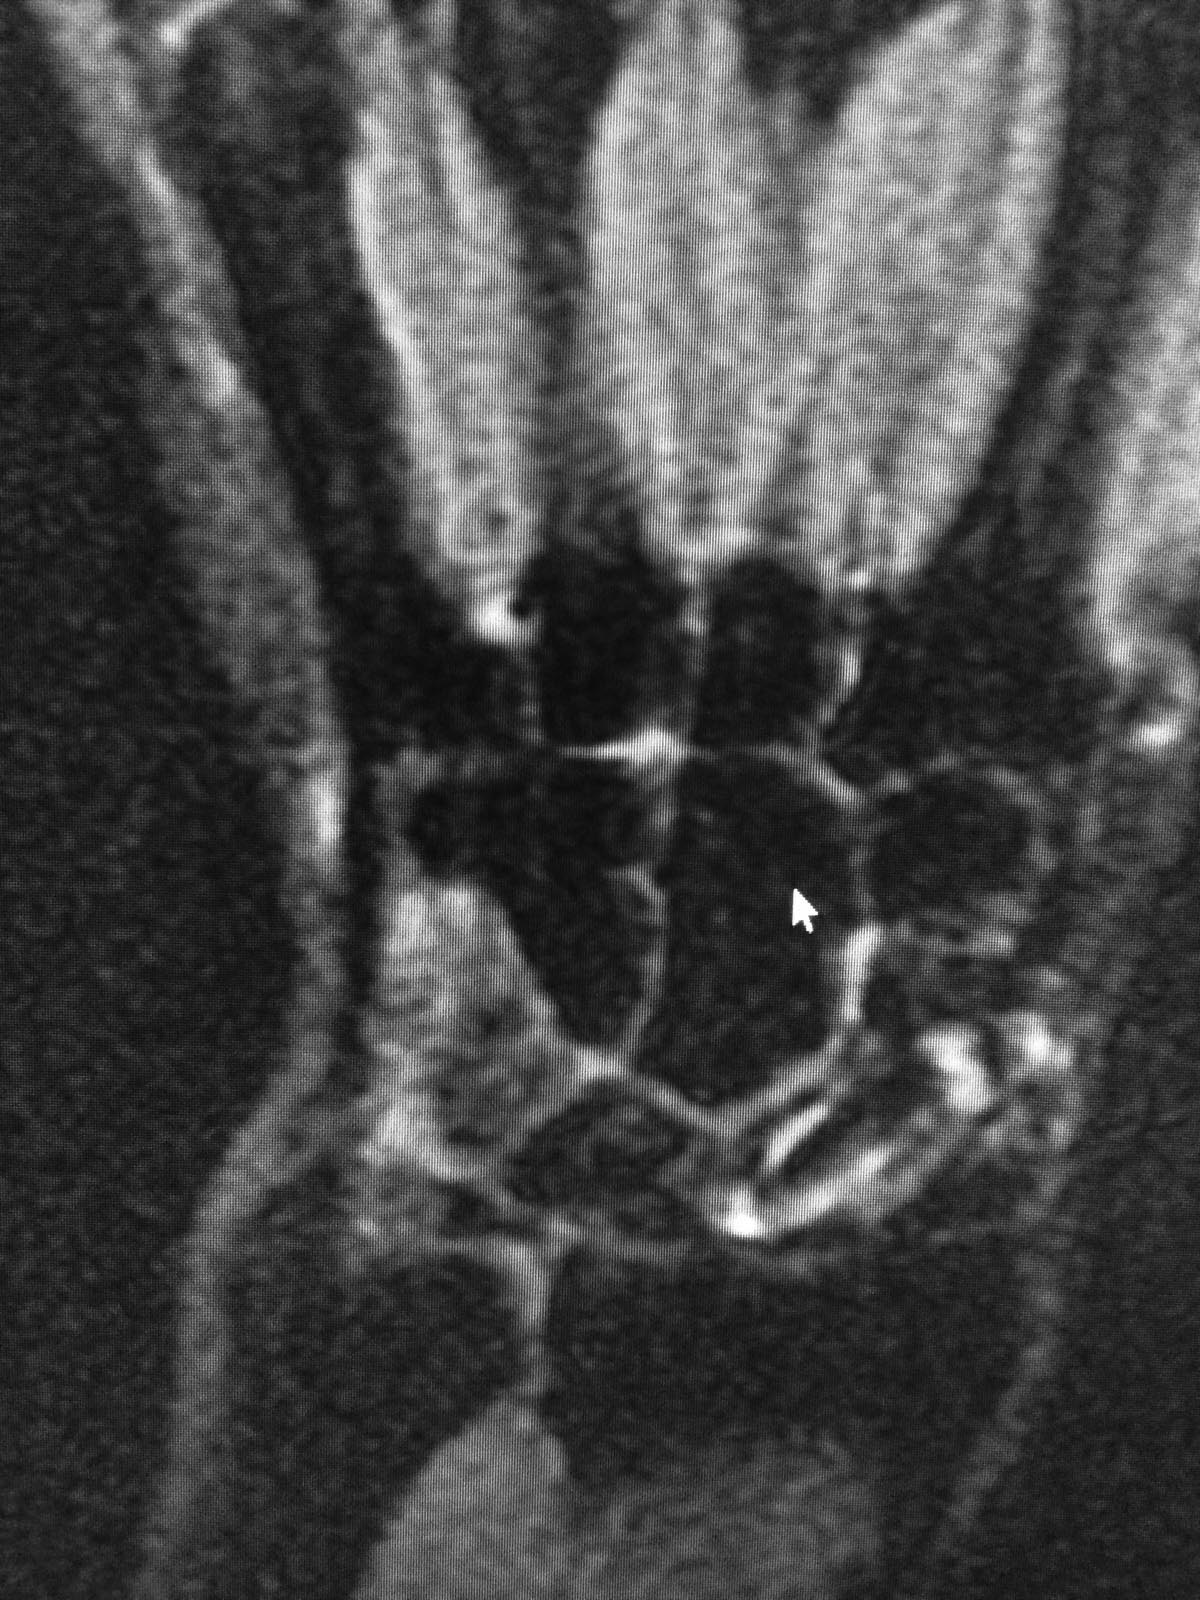

Здравствуйте. Мужчина 30 лет. Травма около 5ти лет назад, МОС винтом, в

данное время в проекции ладьевидной кости болей нет, осевая нагрузка на

1ю пястную кость безболезненная, боли беспокоят при пальпации в проекции

трехгранной кости и движениях в лучезапястном суставе (при пассивных и

активных движениях возникают острые боли, так же в проекции

трехгранной кости). На МРТ отмечаются проблемы в этой зоне. Со слов